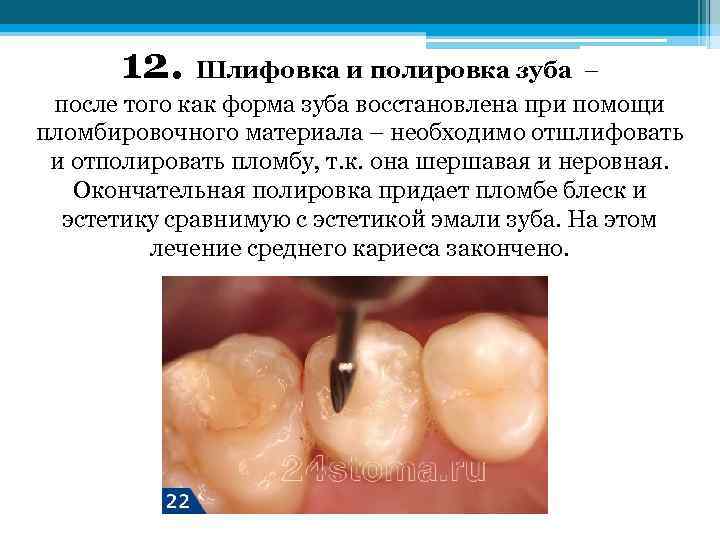

12. Шлифовка и полировка зуба – после того как форма зуба восстановлена при помощи пломбировочного материала – необходимо отшлифовать и отполировать пломбу, т. к. она шершавая и неровная. Окончательная полировка придает пломбе блеск и эстетику сравнимую с эстетикой эмали зуба. На этом лечение среднего кариеса закончено.

12. Шлифовка и полировка зуба – после того как форма зуба восстановлена при помощи пломбировочного материала – необходимо отшлифовать и отполировать пломбу, т. к. она шершавая и неровная. Окончательная полировка придает пломбе блеск и эстетику сравнимую с эстетикой эмали зуба. На этом лечение среднего кариеса закончено.